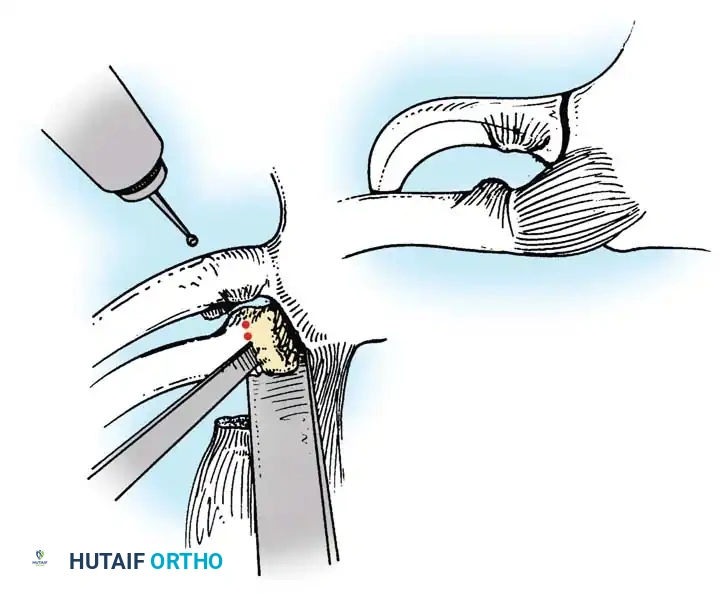

Below is a classic radiographic progression demonstrating the severe sequelae of a posterior hip dislocation:

FIGURE A: Initial anteroposterior radiograph demonstrating a posterior dislocation of the hip. Note the superior and lateral displacement of the femoral head relative to the acetabulum.

- Reduction: For posterior dislocations, a towel clip is placed around the medial clavicle to apply anterior and lateral traction. A blunt periosteal elevator can be carefully inserted behind the clavicle to lever it anteriorly.

- Reconstruction (Figure-of-Eight Technique):

- Drill holes are carefully created in the medial clavicle and the manubrium. A drill guide and retractor must be placed posterior to the bone to protect the mediastinum.

- Heavy, non-absorbable tape (e.g., FiberWire) or a tendon autograft/allograft (such as a semitendinosus or gracilis graft) is passed through the drill holes in a figure-of-eight fashion.

- The graft or suture is tensioned and tied with the joint held in anatomic reduction.